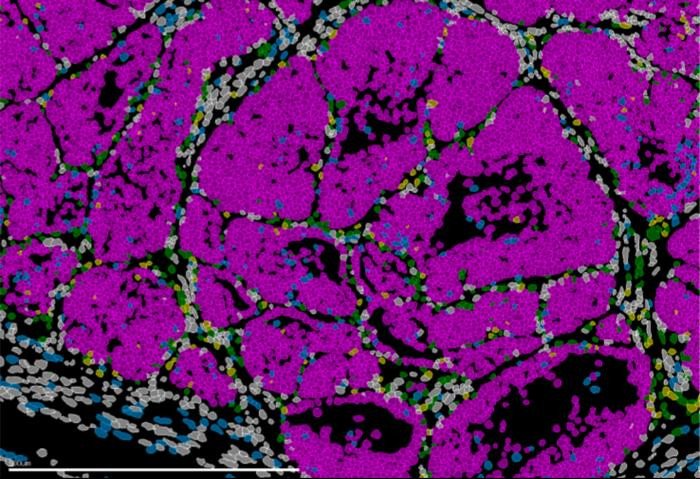

Чтобы прийти к таким выводам, команда использовала генетические модели мышей, анализ отдельных клеток, исследования хроматина и методы пространственной транскриптомики, которые позволяют наблюдать за организацией и поведением клеток непосредственно в опухолевой ткани. Исследователи проанализировали образцы тканей пациенток с раком молочной железы и выявили схожие паттерны экспрессии Prrx1, что позволяет предположить, что описанный механизм может иметь непосредственное отношение к классификации опухолей и клиническому прогнозу.